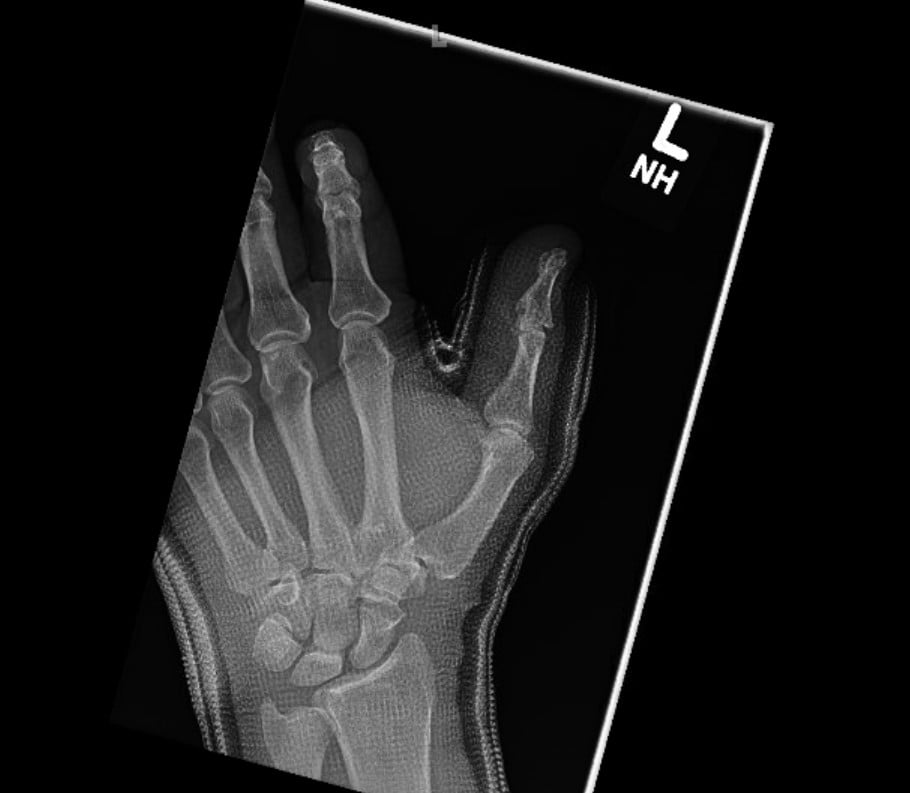

Radiographs were obtained including anterior-posterior and lateral views of the left thumb which demonstrated a penetrating injury of a metallic object (in this case, the threaded nail). The nail on X-ray did appear to pierce the base of the distal phalanx with extension through the interphalangeal joint into the thumb proximal phalanx with an associated vertically oriented split fracture of the proximal phalanx, evident with increased radiolucency on these films. No gas within the soft tissues or other identified foreign bodies; fractures, dislocation, or other acute bony abnormalities were noted. The hospital site has an orthopedic surgery residency program, and the orthopedic surgery resident was consulted given the bony involvement and the recommended outpatient management with an orthopedic hand surgeon.

Post-foreign body removal with cast application X-rays were obtained which redemonstrated the vertically oriented, longitudinal fracture of the left thumb proximal phalanx extending into the interphalangeal joint. Removal of the foreign metal nail also allowed for appreciation of an intra-articular fracture at the distal ulnar aspect of the proximal phalanx where the metallic nail had been previously located, and a distal phalanx base fracture as well. No retained metallic foreign bodies were identified. Of note, there was no involvement of the metacarpal phalangeal joint of the thumb, making this an isolated injury involving only a single joint of the thumb.